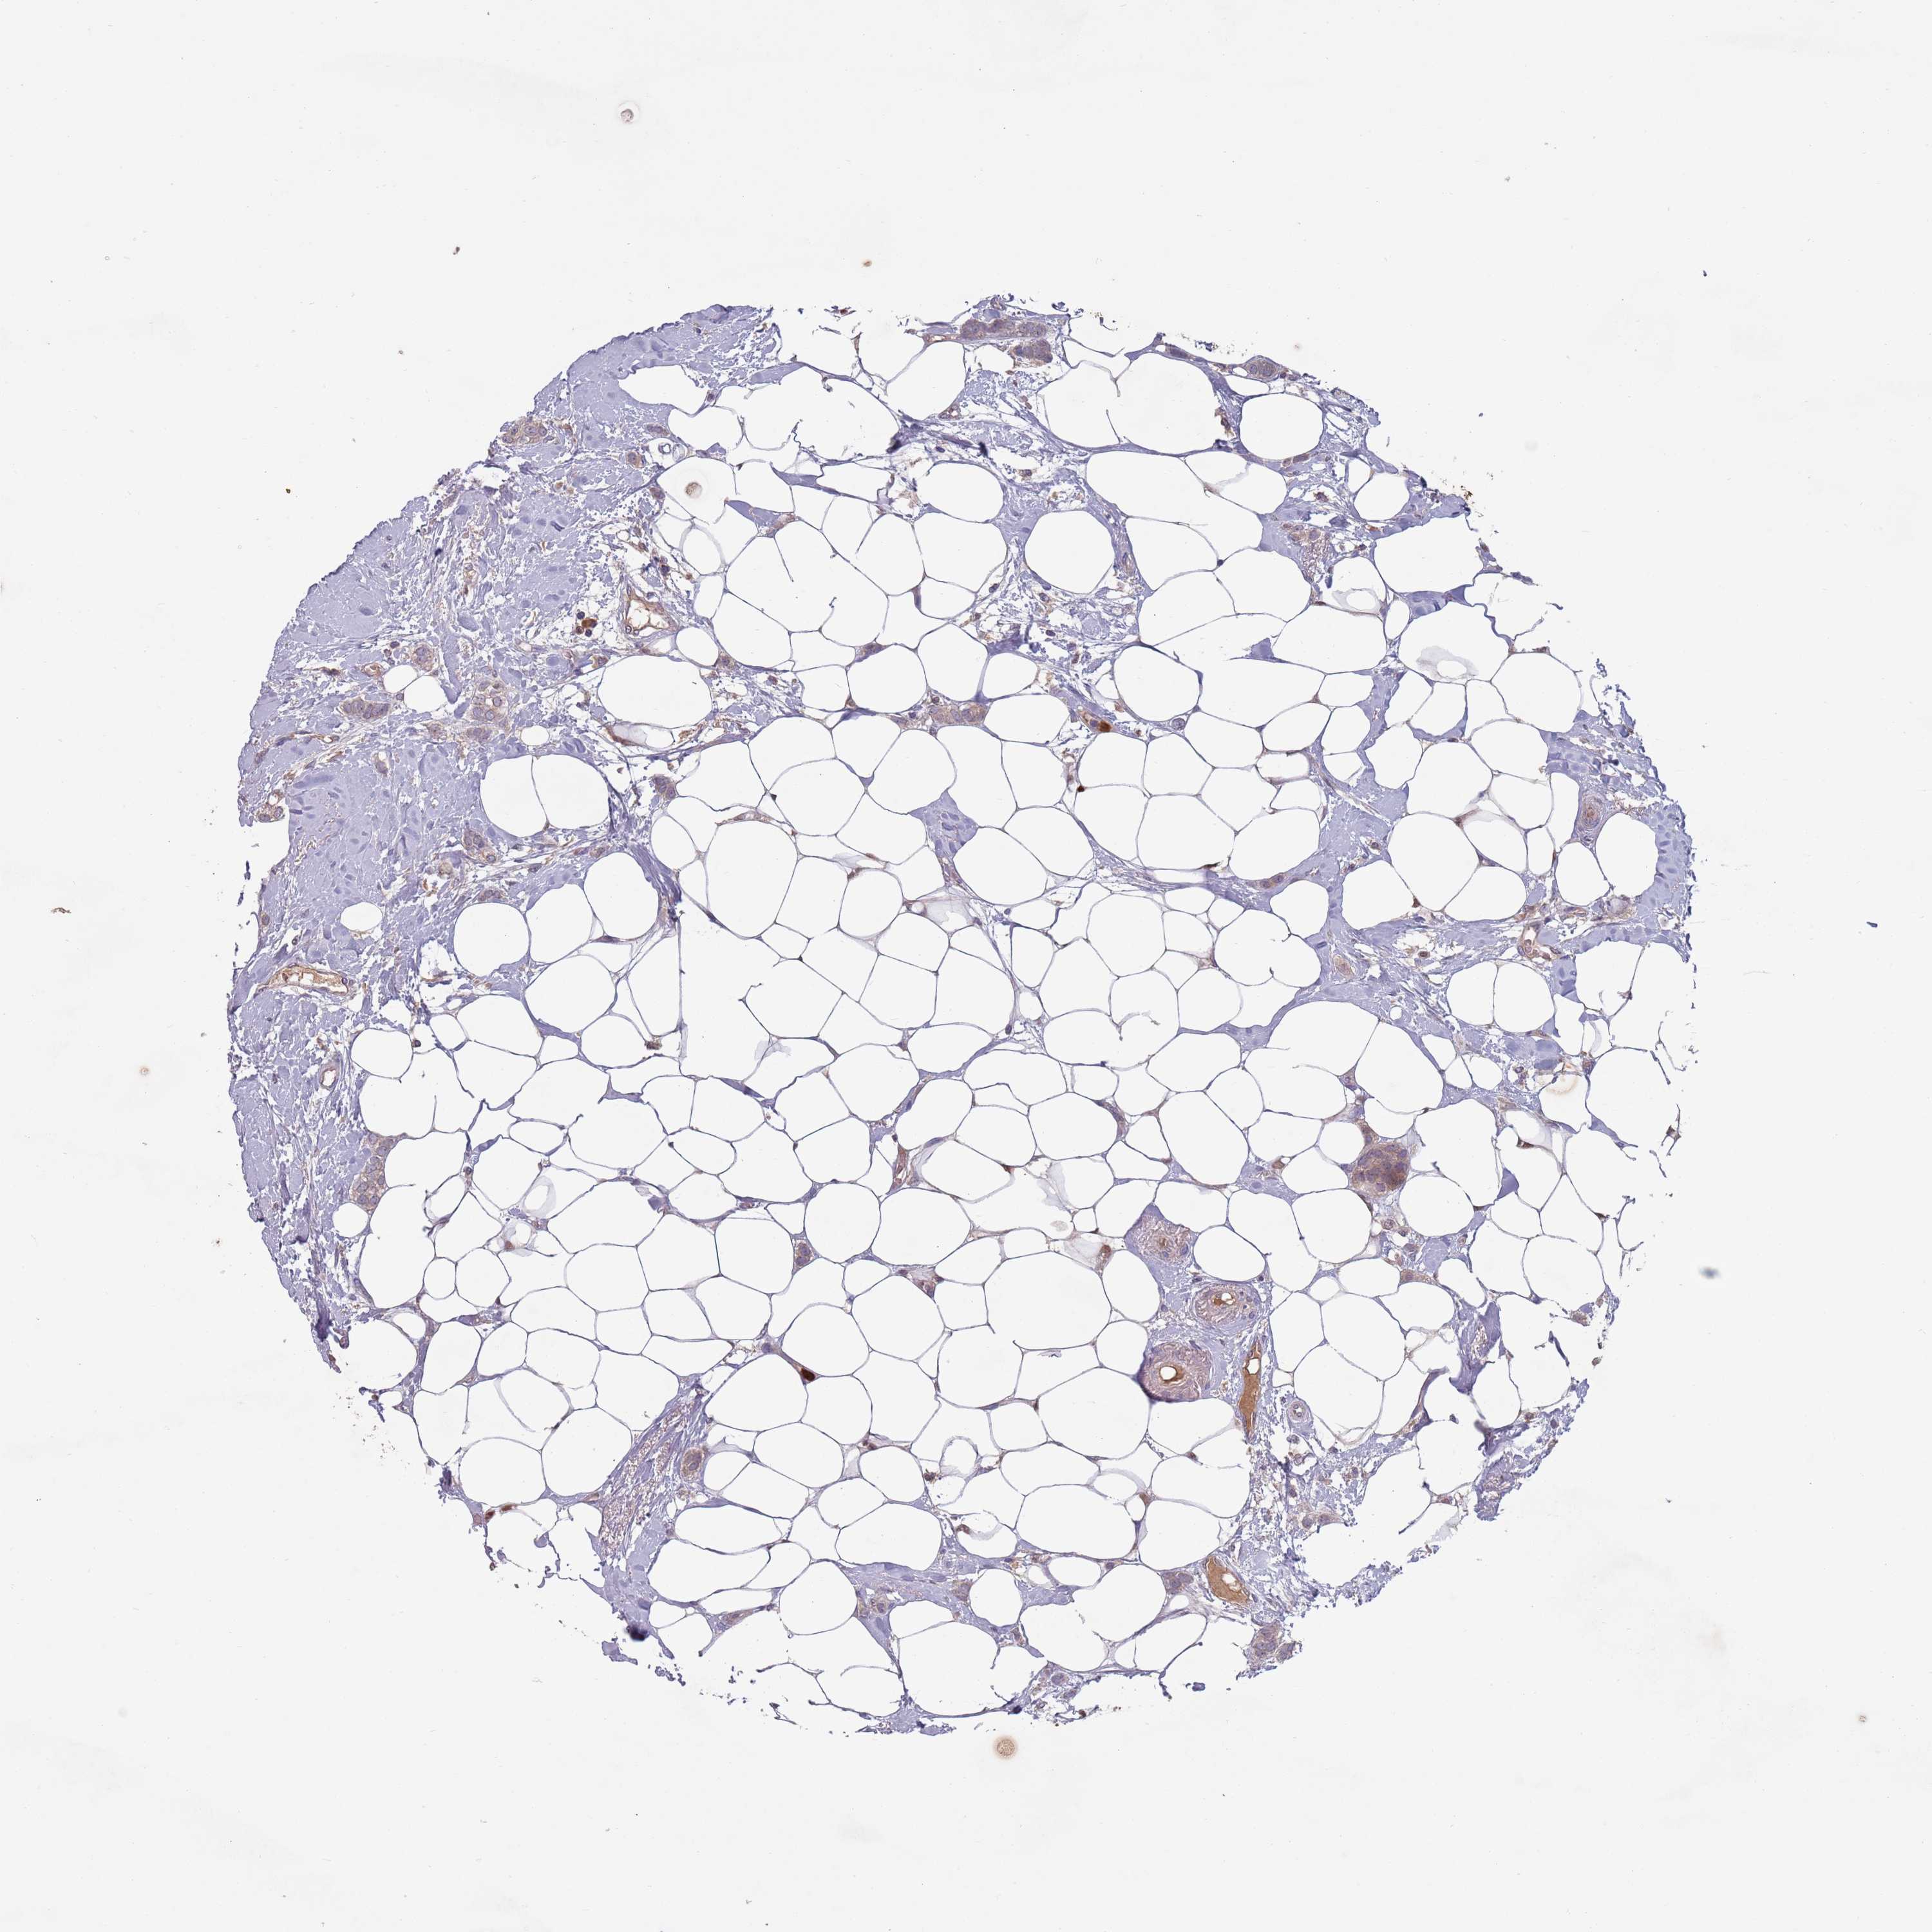

CANCER BREAST CANCER Show tissue menu

BRCA TCGA BRCA VALIDATION PROTEIN EXPRESSION

Breast cancer

Human cancer

Breast invasive carcinoma

TYW1B is not prognostic in Breast Invasive Carcinoma (TCGA)